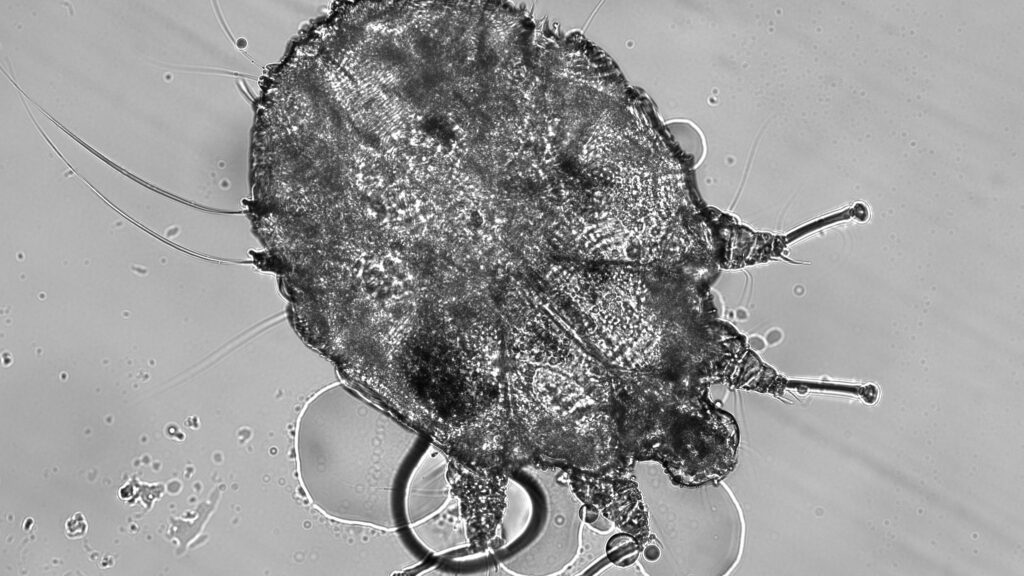

Scabies Mites: The Burrowing Invaders

Unlike demodex mites, which are normal residents of human skin, scabies mites (Sarcoptes scabiei var. hominis) are always considered parasites causing a condition requiring treatment. These microscopic arachnids burrow into the outer layer of skin, creating tunnels where females lay eggs and trigger intense itching, particularly at night. Scabies infestations often concentrate in skin folds like between fingers, around wrists, in armpits, or along the belt line, creating characteristic serpentine burrows visible under magnification. Historically, scabies has affected humans for thousands of years, with descriptions dating back to Aristotle’s time and documented treatments throughout medieval medical texts. While primarily transmitted through prolonged skin-to-skin contact, scabies can sometimes spread through shared bedding or clothing, making it particularly problematic in institutional settings like nursing homes, prisons, and overcrowded refugee camps.